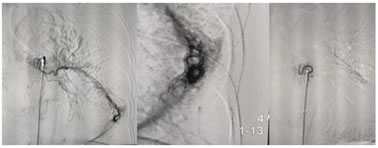

Figure 1:

CASE1: Bronchial artery embolisation in a case of pulmonary koch's. A-Bronchial angiogram showed hypertrophied two bronchial arteries with common trunk on right side with abnormal blush in right lower lobe.

1. selective cannulation of superior bronchial artery for embolisation with 500 micron PVA particles. C-post embolisation of superior branch, only proximal trunck is seen, rest of the artery is completely embolised with PVA particles. D-post embolisation of inferior bronchial artery with patent stump.